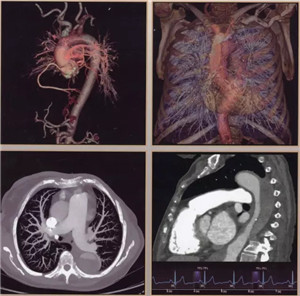

日前,辽阳市中心医院引进当今医学界最先进超高端的美国GE公司生产的Revolution CT(512层)正式投入使用,以此为标志,我市医学影像诊断技术进入超高清时代。该CT是当今世界上临床性能最为强大的CT,它以“合三为一、集大成”的特点引领着CT扫描领域在能谱、速度、宽度方面的国际潮流。落户于中心医院的该CT设备,是东北第三台,辽宁省第二台,目前中国医科大学附属第一医院、盛京医院尚无此种设备。

512层Revolution CT是目前业内探测器最宽、扫描速度超快、射线剂量超低、图像超清晰,且能进行能谱成像的后超高端CT,被称为“革命性”的CT。它实现了——

扫描范围最大:16厘米宽体宝石探测器,心脏、颅脑、肝脏等单器官检查一次扫描就可实现全覆盖;

图像分辨超清:0.23毫米的空间分辨率,对于2毫米冠脉支架的细节和支架内再狭窄清晰可辨;可超早期发现微小肿瘤病变。

扫描速度超快:仅需0.28秒,不受心率快慢限制,只需一个心跳即完成精准的心脏CT检查,成为无创确诊冠心病的最佳检查手段。